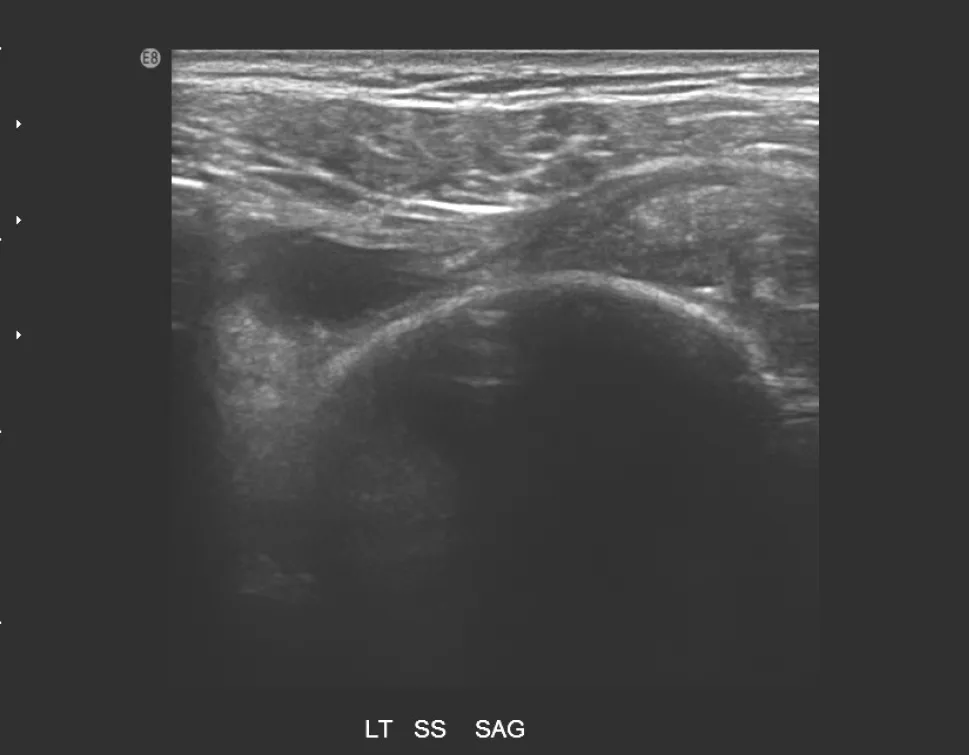

【106-1 醫學(六) 第72題】85歲女性患者,主訴左肩疼痛超過6個月,有局部壓痛,無肌肉萎縮現象,圖為左肩部超音波檢查,上圖為旋轉環帶長軸切 面,下圖為短軸切面,最可能之診斷為何?

詳解

破題關鍵

這題的解題核心在於辨識超音波影像中,棘上肌腱(supraspinatus tendon)出現的明顯缺損與纖維不連續性,這直接指向肌腱斷裂。

選項拆解

-A:錯在風濕性關節炎在超音波下主要表現為滑膜增厚、關節積液、骨侵蝕等,而非肌腱的局部斷裂缺損。